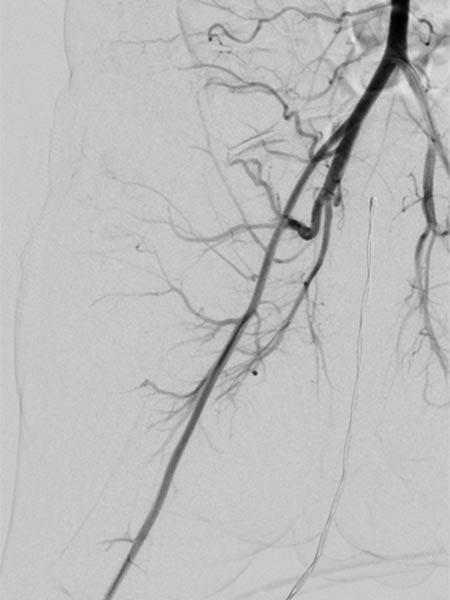

In view of massive coagulopathy prohibiting open surgery in this location and lack of improvement with drug therapy and replacement of platelets and coagulants alone, the decision was made to embolize the hypervascularized tumor. Digital subtraction angiography (DSA) shows the highly vascularized tumor supplied mainly from the right superior gluteal artery.

The tumor shows the typical tumor blush with diffuse, strong contrast enhancement on DSA after super-selective catheterization with the microcatheter.

Via the microcatheter, the tumor is now gradually embolized super-selectively with particles 150 microns in size via the supplying arterial branches.

In the control DSA, the main part of the tumor has now been successfully embolized and cut off from the circulation. Only very cranial tumor-supplying branches remained at this stage of the embolization.

In the final control angiography with long series after injection into the right common iliac artery, the tumor is completely devascularized. The unaffected, physiological arterial branches of the surrounding tissue are all preserved. Thus, the tumor is completely eliminated from the circulation. Activation of coagulation and consumption of platelets in the tumor has stopped.